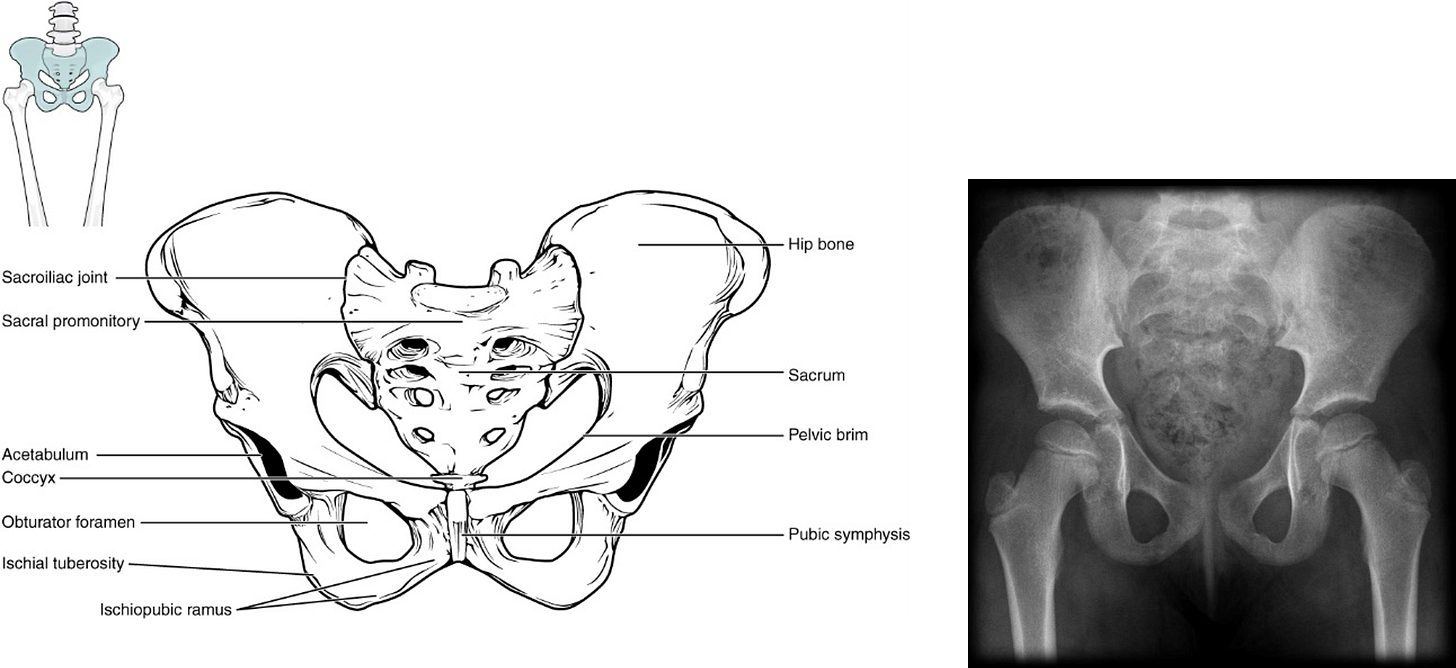

Each pelvic bone (os coxa) is actually 3 bones (ilium, ischium, and pubis) fused together. These bones usually fuse together by 7-9 years of age. In the radiograph of a child’s pelvis (click for source) on the right, you can see the bones are unfused. In the back (posteriorly), each os coxa forms a joint (sacroiliac joint) with the sacrum. In the front (anteriorly), the ossa coxae are united by a piece of fibrocartilage, forming the pubic symphysis. Anatomical features of the female pelvis (below) serve to widen the birth canal to facilitate childbirth.